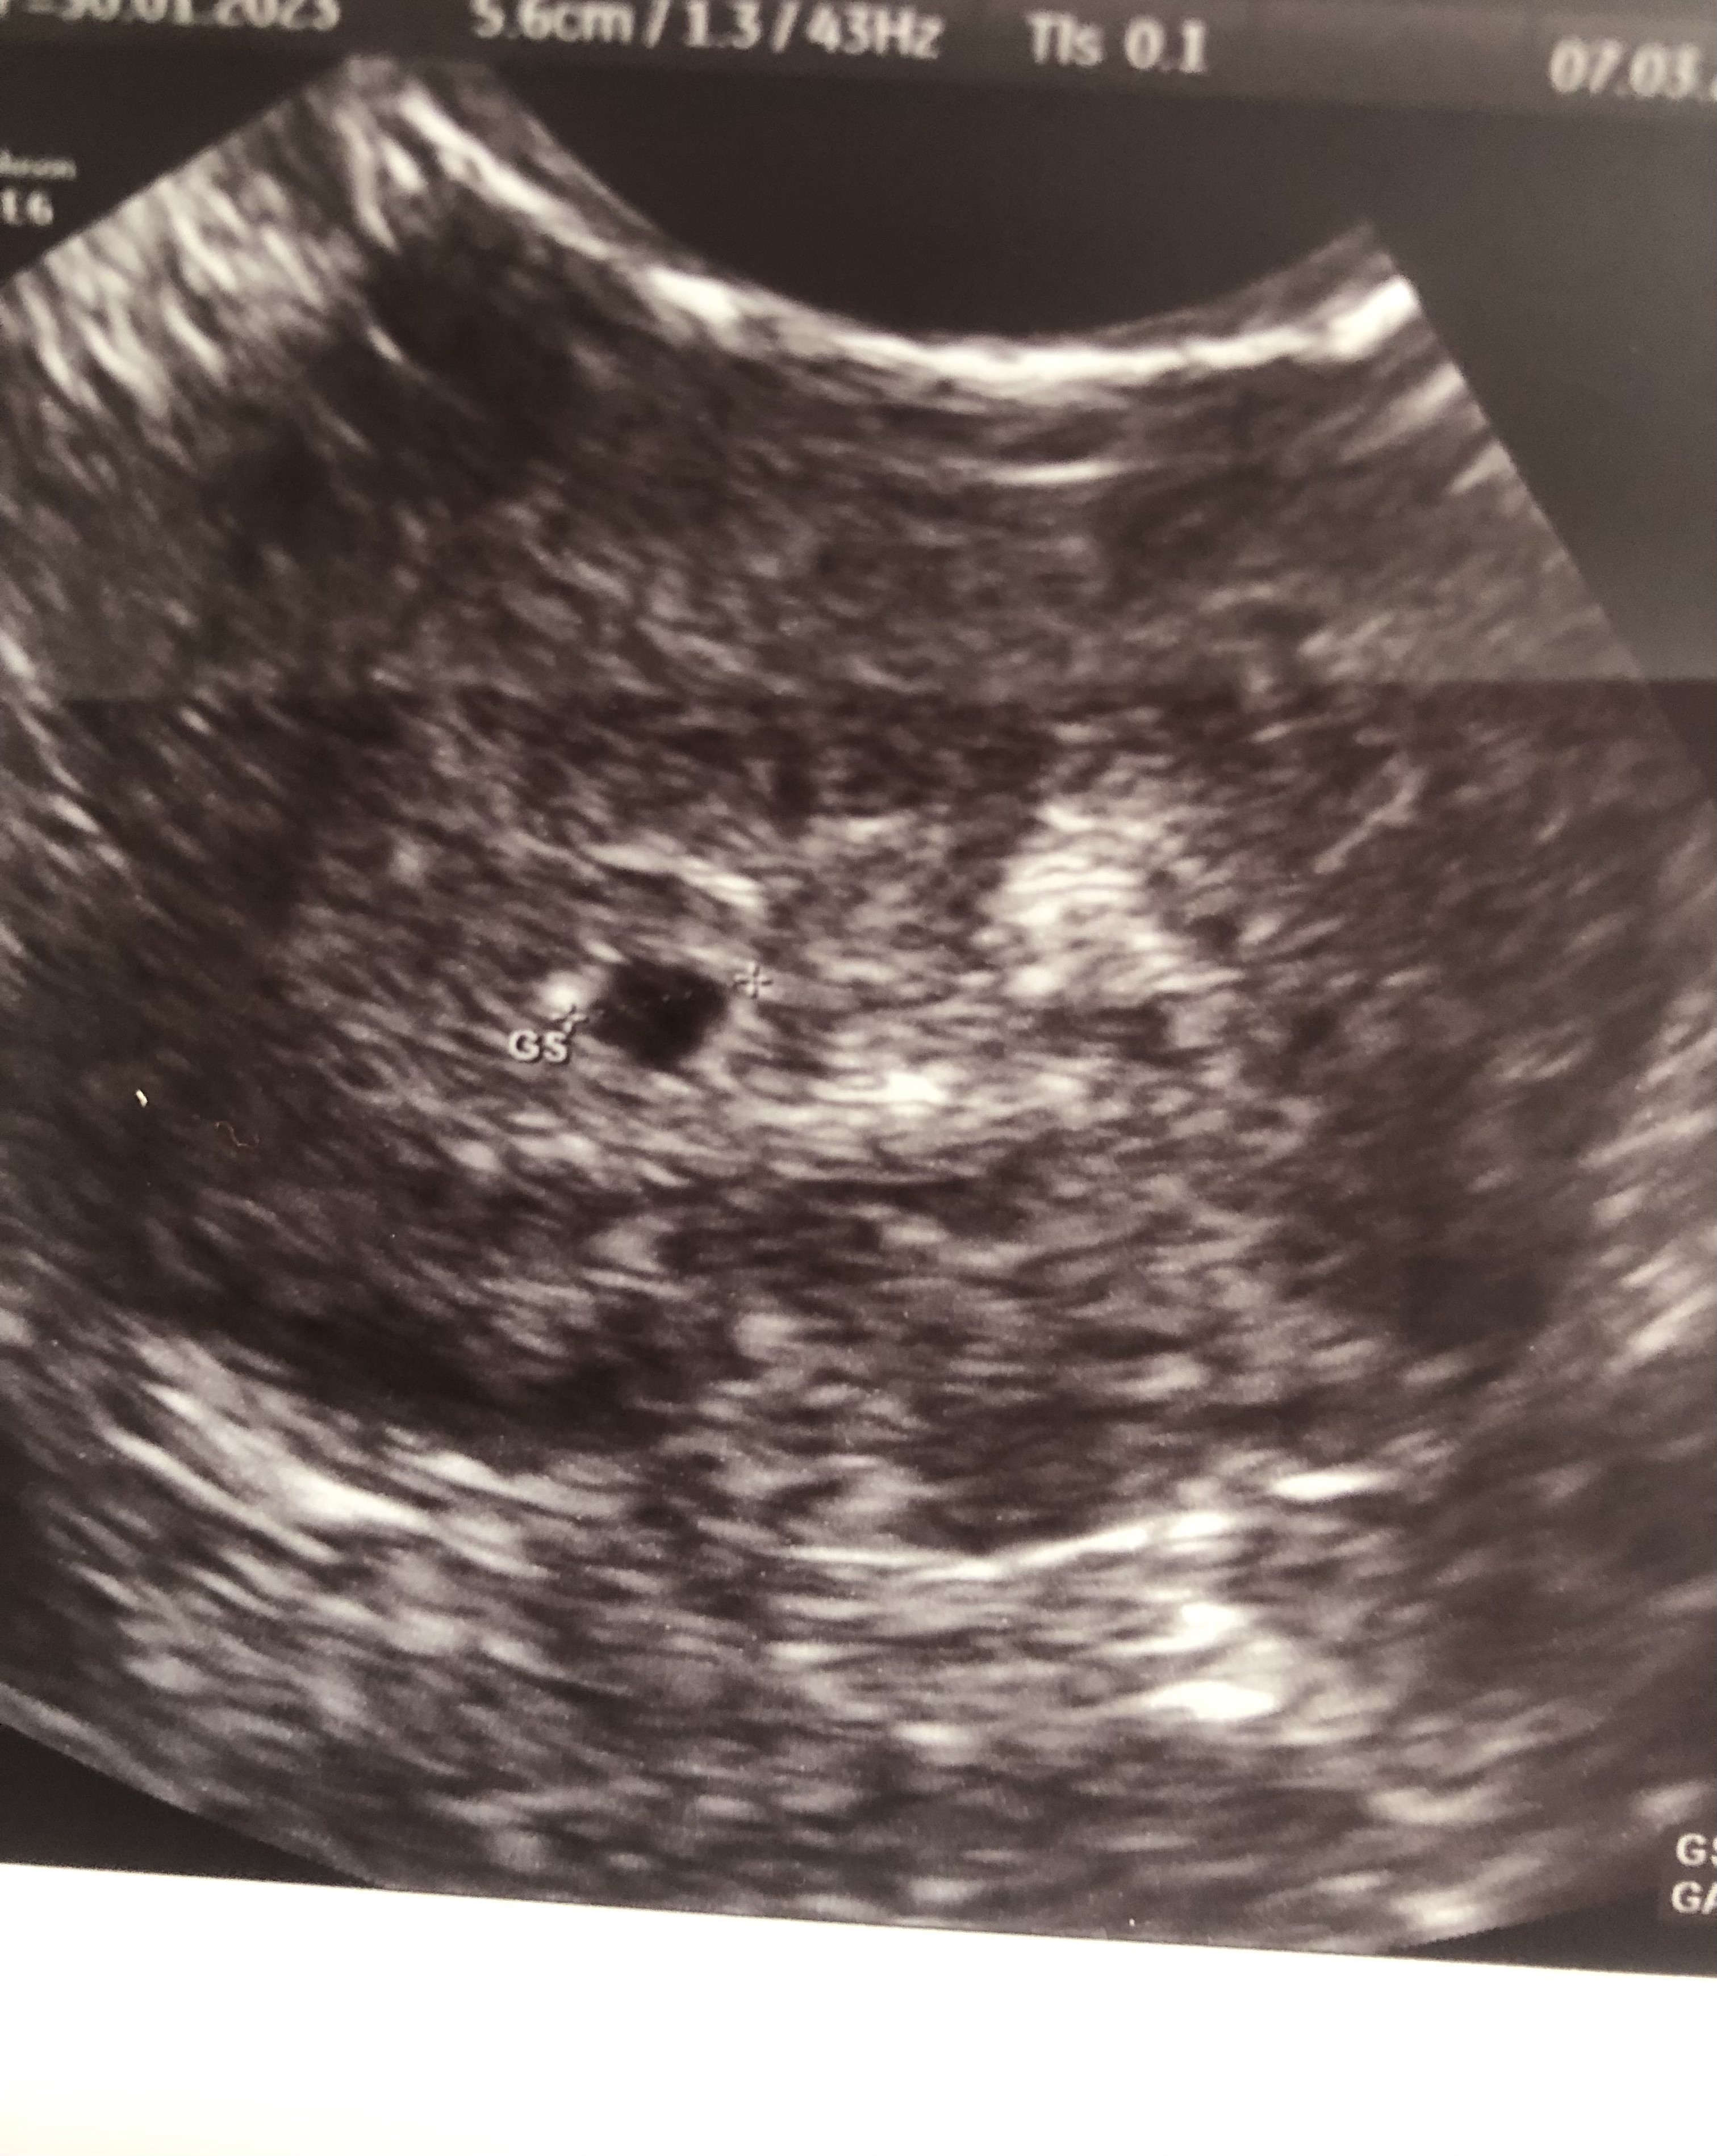

Dziewczyny, które były na USG w 5+0 lub coś koło tego - co było widać na USG? Był już pęcherzyk?

ja miałam badanie w 5+3, był pęcherzyk. Zostawiam zdjęcie jak to wyglądało

Załączniki

• IMG_0786.jpeg